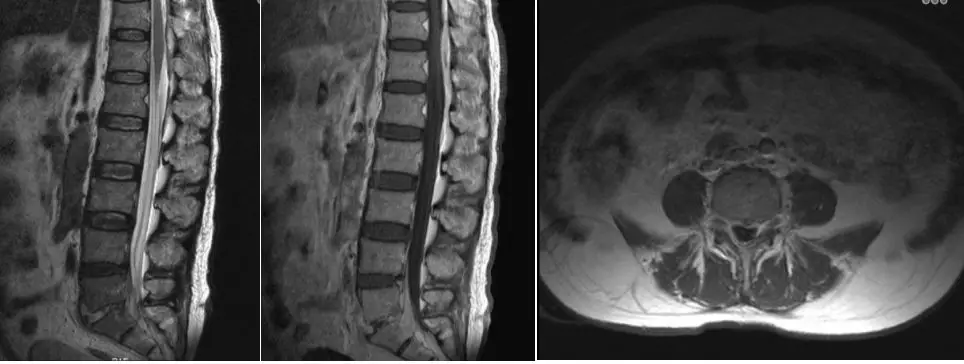

入院后查超敏C-反应蛋白60.4mg/L,白细胞计数17.3×10^9/L。腰椎MRI:T11-L2水平硬膜背侧及L4-S1椎体后方硬膜外占位,部分呈囊性,增强扫描呈明显不均匀强化;L5/S1椎间隙变窄并见椎体弥漫性信号异常,呈明显强化(图1)。诊断考虑L5S1椎间隙感染合并硬膜外脓肿形成。

图1. 腰椎MRI:T11-L2水平硬膜背侧及L4-S1椎体后方硬膜外占位,部分呈囊性,增强扫描呈明显不均匀强化;L5/S1椎间隙变窄并见椎体弥漫性信号异常,呈明显强化。